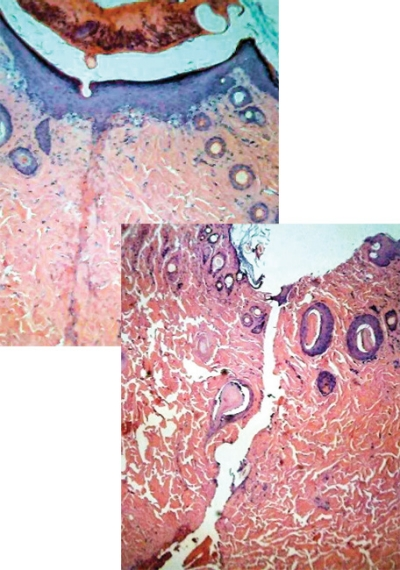

The team reports satisfactory welding on guinea pig aorta and skin tissues using a pulsed-mode fiber laser at 1535 nm. The tensile strength of the welded tissue is very similar to original tissue samples and shows histologically, very little or no evidence of scarring in the welded area. "At the present time, our limiting factor is the speed of the welding, which may be addressed in a variety of ways," says IUSL director Robert Alfano.

The researchers were able to qualitatively assess laser welded tissue on the millimeter (mm) depth scale using Raman spectroscopy, which enables monitoring of changes in key protein and lipid molecules in real time during the LTW process. The Raman spectrum indicates average contributions from different layers of the tissue, and gives an average probe of skin, arteries and aorta.

The Raman approach monitors underlying molecular changes from the degree of thermal damage and protein denaturation before and after laser application—enabling evaluation of changes in the local structure of collagen and elastin and the role of water in the collagen helical structure. The method revealed that "the Amide I peak intensity and height for collagen and gelatin are different," according to researcher Stephane Lubicz. "Changes in corneal collagen due to aging and heat denaturation are characterized by the broadening of the amide I and III bands; conversion of reducible cross-links to non-reducible cross-links in collagen resulted in an increase in the Raman intensity at specific wavelengths."